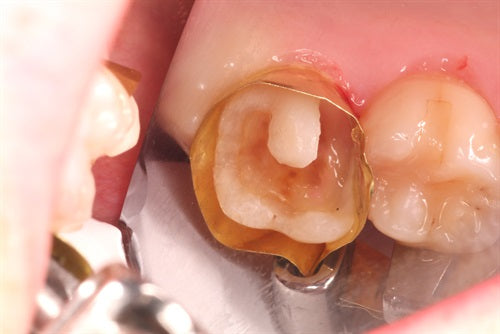

#16 Large composite by Dr. Ahmad Fayad

The below case was completed and documented by our guest presenter, Dr. Ahmad Fayad. This is a great example of a Greater Curve band and technique at work! Introduction: In... Read More